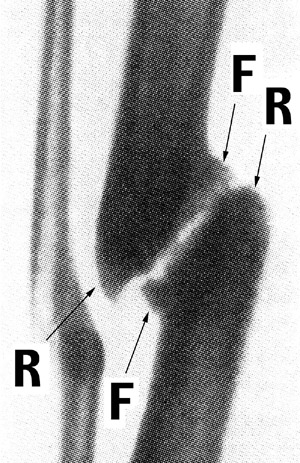

Figure 3B: X-ray of oblique pseudarthrosis (3) Areas of bone formation (F) and resorption (R) at periosteal corners of fracture ends (marked by authors) corresponding to locations of hydrostatic tension and high hydrostatic pressure, respectively, in Models I and II.